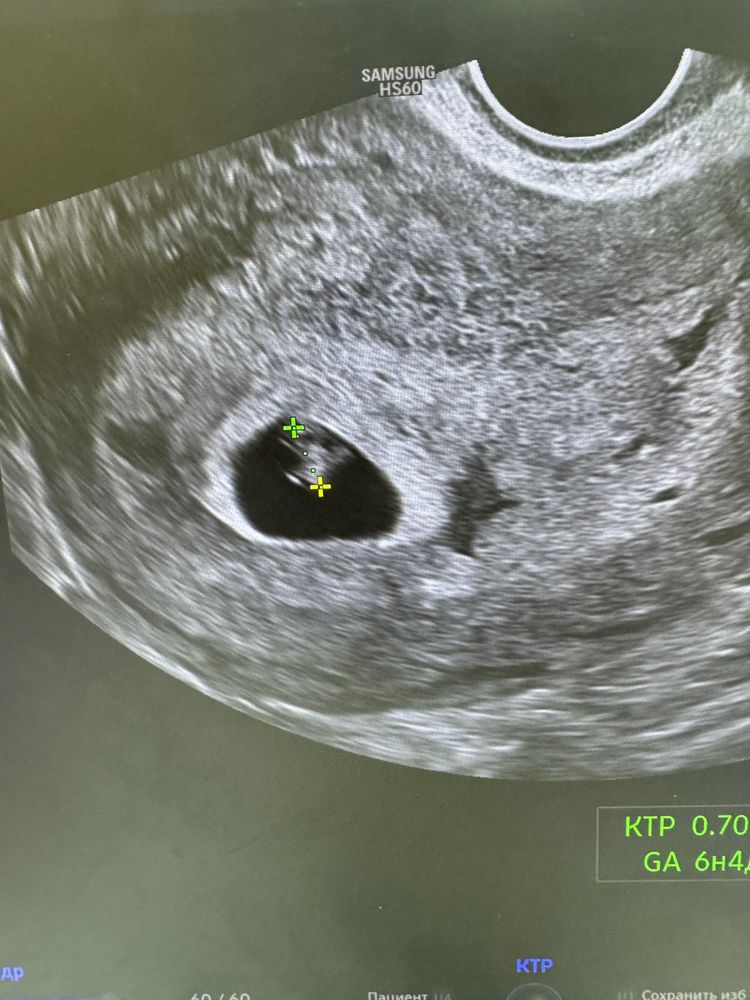

УЗИ ровно 7 недель и 7 мм малыш(ка)

А по размеру определили, что это 6+4, а не 7.